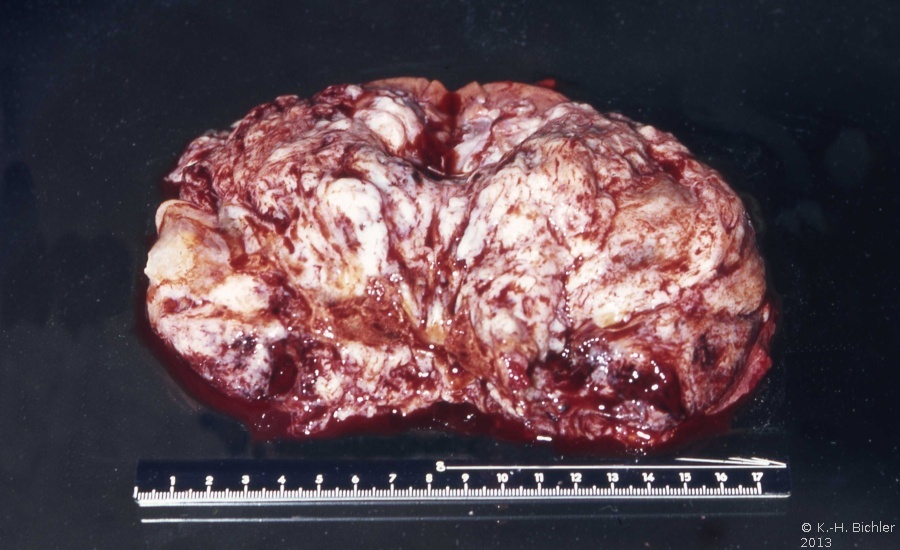

Auf der Schnittfläche ist der Tumor von gelbbrauner bis grauer Farbe mit einzelnen Einblutungen. Zystische Anteile und Nekrosen kommen vor sowie oberflächlich glatte, knotenförmige Strukturen, ähnlich einem Rhabdomyosarkom (Abbildung 1a-d).